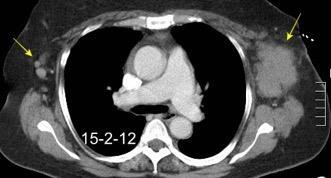

Tumor desmoide derecho. Recidiva.

Tumor maligno. 0,2% de los tumores de mama.

Ocurren en 10% de los implantes de mama.

En los 3 años después del implante.

(Dudas sobre el dato)

Kilmartin C et al. Desmoid Tumor and Implant-Based Breast Reconstruction. Case Rep Oncol. 2023